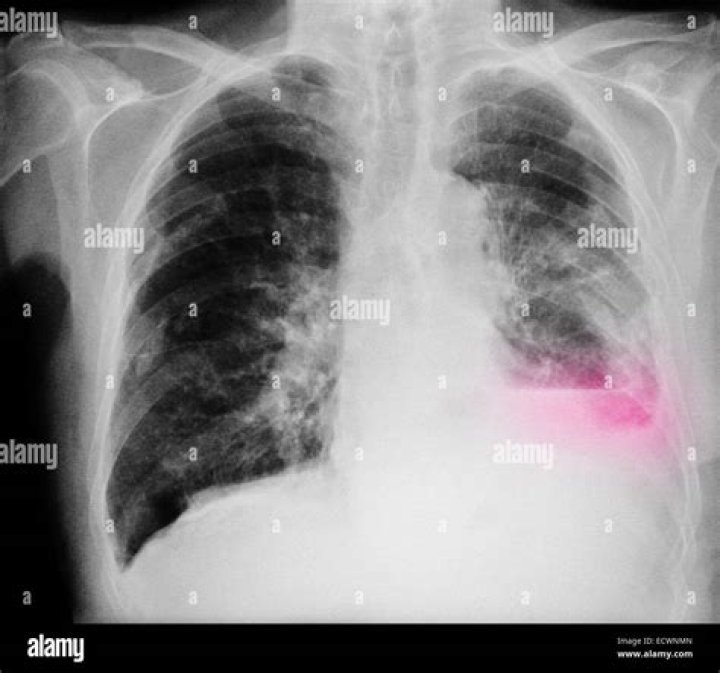

A chest X-ray of someone with lung cancer may show a visible mass or nodule. This mass will look like a white spot on your lungs, while the lung itself will appear black. However, an X-ray may not be able to detect small or early stage cancers.

It is often the first imaging test a healthcare provider will order if lung or heart disease is suspected. If lung cancer is involved, chest X-rays can sometimes detect larger tumors, but more often than not fail to diagnose the disease. Chest X-rays also fall short as a tool for lung cancer screening.

A nodule is a “spot on the lung,” seen on an X-ray or computed tomography (CT) scan. In fact, a nodule shows up on about one in every 500 chest X-rays. Normal lung tissue surrounds this small round or oval solid overgrowth of tissue. It may be a single or solitary pulmonary nodule.

Adenocarcinoma (an NSCLC), the most common type of lung cancer, which occurs in about 30% to 40% of all cases. A subtype of adenocarcinoma is called bronchoalveolar cell carcinoma creates a pneumonia-like appearance on chest X-rays.

An X-ray image of your lungs may reveal an abnormal mass or nodule. A CT scan can reveal small lesions in your lungs that might not be detected on an X-ray. Sputum cytology. If you have a cough and are producing sputum, looking at the sputum under the microscope can sometimes reveal the presence of lung cancer cells.